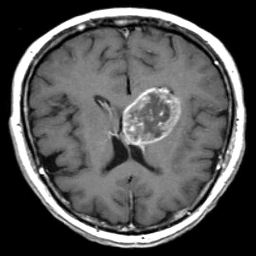

Figure 1: Heatmap Comparison of Unhealthy Images. Different columns show unhealthy MRI images of different positions, sizes, and textures. The first row is the raw image. The second row is the heatmap predicted with PatchCore. The third raw is the heatmap predicted with the proposed method.